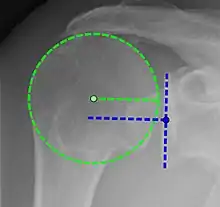

X-ray projectional radiography cannot directly reveal tears of the rotator cuff, a 'soft tissue', and consequently, normal X-rays cannot exclude a damaged cuff. However, indirect evidence of pathology may be seen in instances where one or more of the tendons has undergone degenerative calcification (calcific tendinitis). The humeral head may migrate upward (high-riding humeral head) secondary to tears of the infraspinatus, or combined tears of the supraspinatus and infraspinatus.[51] The migration can be measured by the distance between:

- A line crossing the center of a line between the superior and inferior rims of the glenoid articular surface (blue in image).

- The center of a "best-fit" circle positioned over the humeral articular surface (green in image)

Normally, the former is positioned inferiorly to the latter, and a reversal therefore indicates a rotator cuff tear.[51] Prolonged contact between a high-riding humeral head and the acromion above it may lead to X-ray findings of wear on the humeral head and acromion; secondary degenerative arthritis of the glenohumeral joint (the ball and socket joint of the shoulder), called cuff arthropathy, may follow.[50] Incidental X-ray findings of bone spurs at the adjacent acromioclavicular joint may show a bone spur growing from the outer edge of the clavicle downward toward the rotator cuff. Spurs may also be seen on the underside of the acromion, once thought to cause direct fraying of the rotator cuff from contact friction, a concept currently regarded as controversial.